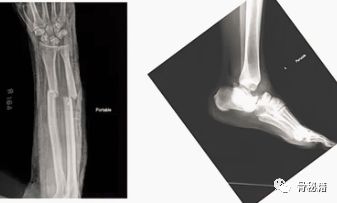

现在来了两个开放骨折,一个前臂,一个距骨,我应该怎么处理?什么时候我需要急诊手术呢?开放骨折、肢体毁损、没有动脉搏动、多发伤患者一个放开骨折来了我需要做什么呢?